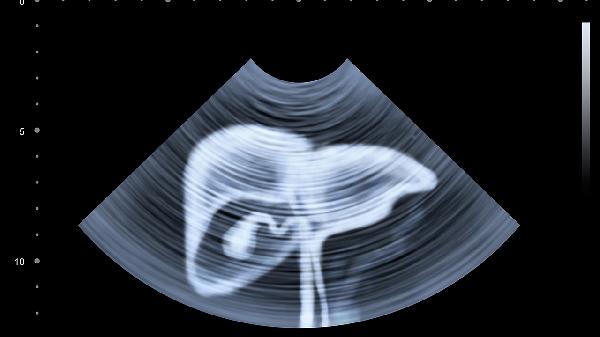

2、影像学检查提供肝脏形态和内部结构的直观信息。B超是首选的筛查手段,可发现肝脏大小、形态、回声等异常,识别囊肿、肿瘤或脂肪肝。CT和MRI扫描分辨率更高,对肝癌、肝硬化和血管病变的诊断有重要意义。增强扫描可进一步观察病灶的血供特点,帮助鉴别良恶性病变。